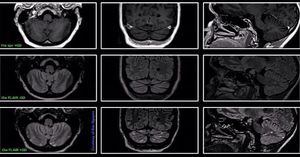

Contrast-enhanced 3D SPACE FLAIR imaging seems to improve detection of leptomeningeal disease when compared with contrast-enhanced 3D T1-w SPACE imaging. Images courtesy of Bac Nguyen.